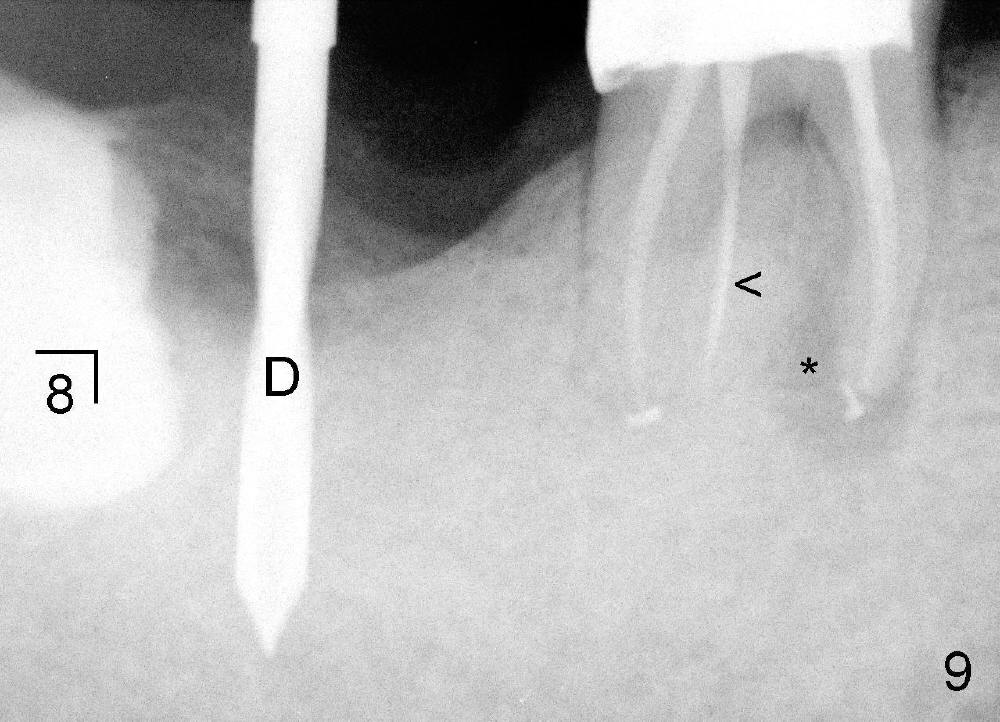

五十来岁郑先生缺失两个下颌第二磨牙,严重牙齿磨耗,三年前主诉右下第一磨牙冷热痛(可能与磨耗有关),近中有轻度根尖阴影(图一箭头),初步CT检查表明该牙齿有四个根管(图二,三),兴高采烈,这样不会错过远中舌侧根管(DL),开髓发现根管几乎阻塞,尤其是远中舌侧,hand files不容易进入根尖,使用20/.04 rotary file时,在根尖断裂(图四箭头,其余根管插入30/.06牙胶尖),一时不能bypass断针,暂封。十二天后,重新bypass断针,终于成功,但是取不出断针,扩大二十号hand file(远中舌侧根管),图五,图六侧方充填(lateral condensation)之前,图七之后(图六,七*:近中阴影)。根管治疗和牙冠之后一直无症状,一年半在第二磨牙处植牙(图八I),虽然第一磨牙近中根尖阴影增大(*),但离植牙还有一定距离,可能不会产生问题。不过不久植牙松动,病人自己取出,可能当时钻洞太大,而不够深(no primary stability),怕侵犯下颌神经(图八红线)。十个月后再次试图植牙(图九D:钻头),突然发现智齿(阻生)在手术视野之中,而且智齿咬合面不干净,结果取消植牙,把智齿拔除,这时病人第一磨牙仍没有症状,但是根尖阴影不可观(图九*),远中舌侧根尖好像没有病变(箭头)。大概这次智齿拔除也与左下智齿七拔除(左下第二磨牙植牙之前)一样不舒服,郑先生一直没有回来做右下第二磨牙植牙。上周六他终于登门,右下第一磨牙出现根尖脓肿症状(术后近三年),根尖片如图十。S代表已经愈合智齿牙槽窝,根尖阴影不小,断针根尖仍没有阴影。